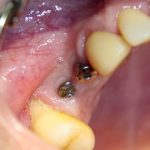

Давным давно, года, эдак, четыре назад, пришла ко мне пациентка. Из-за длительного отсутствия зубов и особенностей строения костной ткани, в боковом участке нижней челюсти произошла такая атрофия, что в её родном городе ей рекомендовали забыть об имплантатах: